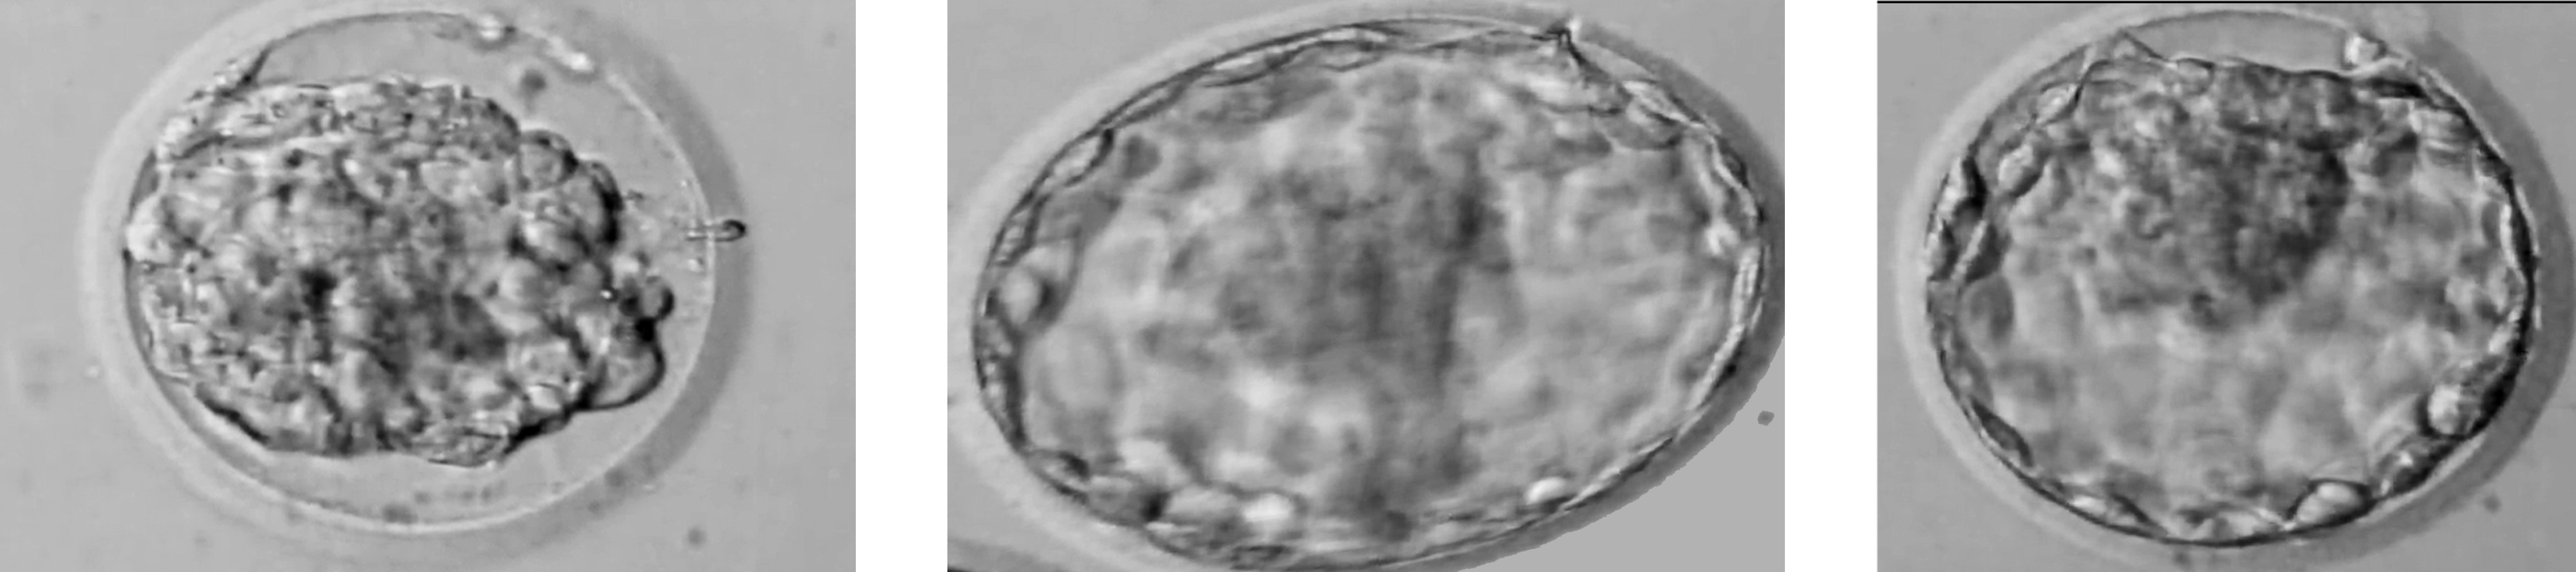

Embryo reexpansion does not affect clinical pregnancy rates in frozen Frozen Embryo Re Expansion Using the scoring method developed by gardner and. A garcía esteve, m escribá suárez, m alavés navarro, d gonzález abreu, m lozano zamora, v lópez martínez, j aibar manero, c. With supernumerary frozen embryos, the goal is to transfer the best embryos first. Frozen Embryo Re Expansion.